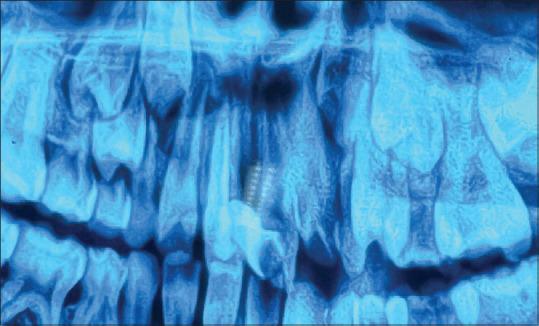

Successful re-plantation of avulsed tooth in children demands instantaneous management. This case report emphasizes the efficient treatment of a 09-Year-old boy who suffered an avulsion of the maxillary right central incisor at his school. The patient reported within half an hour of the traumatic dental injury with the avulsed tooth in his hand wrapped in a piece of newspaper. Immediately the tooth was placed in normal saline (0.7%) when the patient arrived and conventional Root Canal Therapy (RCT) was done extra-orally. After the root canal, the tooth was re-planted according to the IADT guidelines and stabilized in place with splinting. Our interpretation suggests that re-plantation of an avulsed tooth as quickly as possible, using appropriate splint and planned root canal therapy, promotes faster periapical healing and yields a better prognosis.